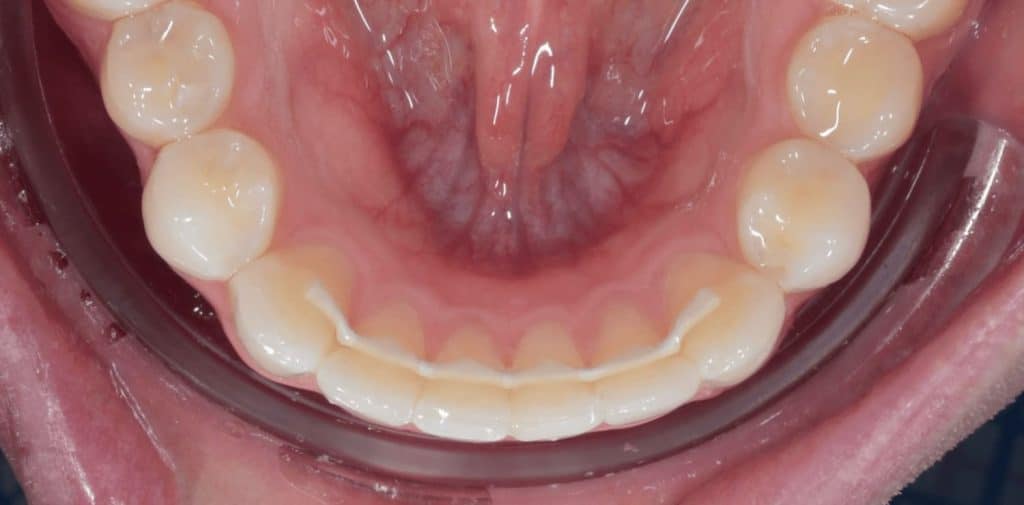

Un fil de contention est un fil fin, discret, collé sur la face interne (linguale ou palatine) des dents, généralement de canine à canine. Il maintient les dents dans leur position corrigée de façon permanente, sans que le patient ait à y penser au quotidien.

Le fil est directement collé à l’aide d’une résine composite biocompatible sur la face interne des dents concernées. Il est totalement invisible lorsque vous souriez ou parlez. Une fois en place, il travaille en silence, 24 heures sur 24, pour garantir la stabilité du résultat obtenu.

Un fil sur-mesure, en revanche, est conçu à partir d’une empreinte ou d’un scan numérique de votre bouche. Il épouse parfaitement la courbure de votre arcade et se positionne exactement là où il doit être, sans exercer de tensions inutiles.

Non. Posé sur la face interne des dents, le fil de contention est totalement invisible lorsque vous parlez ou souriez. Seule une inspection de l’intérieur de la bouche permet de le distinguer.